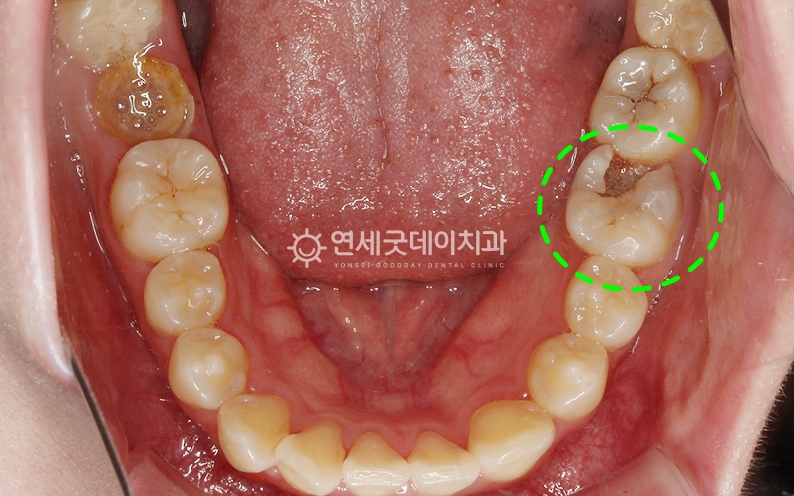

치료 전 환자분의 구강 상태를 보겠습니다. 누가 봐도 안 좋은 상태임을 인지할 수 있는데요.

치아가 없음에도 틀니를 사용하지 않으시고 몇개 남지 않은 치아로 생활을 하셨습니다. 그렇기에 저작력 저하로 인한 소화불량, 치아 상실로 인한 자신감 저하 등 여러 문제가 따라오는 것은 당연한 결과였습니다.

치료 전 촬영한 엑스레이 사진입니다. 남아있는 자연치아를 유지하는 것이 가장 좋지만 환자분의 경우 위쪽에 남아있는 5개의 치아들은 잇몸이 좋지 않아서 잇몸뼈 안에서 치아가 헐겁게 흔들리고 있었습니다. 아래 어금니들 또한 충치가 생겨 더이상 치아를 쓰기가 어려운 상태였습니다.

결국 남아있는 10개의 치아들을 모두 발치하고 전악 임플란트를 해야 했는데요.